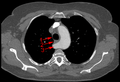

Aberrant subclavian artery at axial CT-scan. (1) trachea, (2) esophagus, (3) Aberrant subclavian artery.